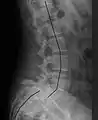

| X-ray of the lateral lumbar spine with a grade III anterolisthesis at the L5-S1 level | |

Classification by degree of the slippage, as measured as percentage of the width of the vertebral body:[14] Grade I spondylolisthesis accounts for approximately 75% of all cases.[6]

- Grade I: 0–25%

- Grade II: 25–50%

- Grade III: 50–75%

- Grade IV: 75–100%

- Grade V: greater than 100%

X-ray of measurement of spondylolisthesis at the lumbosacral joint, being 25% in this example